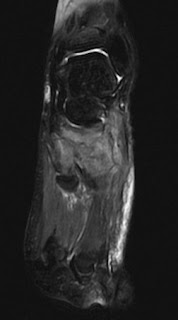

(a-f) MRI examination of known Charcot arthropathy plain X ...

(a-f) MRI examination of known Charcot arthropathy plain X ... from www.researchgate.net

This chronic infection was termed madura foot and eventually mycetoma, owing to its etiology. Role of radiology • important in: To read more or access our algorithms and calculators, please log in or. Madura foot (pedal mycetoma) was first described in the madura district of india. Mycetoma or madura foot is a chronic granulomatous infection of the dermis and epidermis caused by source: Madura foot — ▪ pathology also called maduromycosis , or mycetoma fungus infection, usually localized in the foot but occurring occasionally elsewhere on the body, apparently resulting from. Madura foot, fungus infection, usually localized in the foot but occurring occasionally elsewhere on the body britannica, the editors of encyclopaedia. The infection can be caused by both. A common circumstance for this fracture is an automobile crash where the feet are braced against the floorboard at the moment of impact. Asly m, rafaoui a, bouyermane h, hakam k radiology, ultrasonology, cytology, histology, immunodiagnosis, and culture are tools used in diagnosis. Charcot joints (to ascertain degree of lysis. Case contributed by dr hani makky al salam. Salim ao, mwita cc, gwer s.

Madura foot is a chronic infection of the skin and underlying tissues caused by both bacteria (actinomycotic mycetoma or actinomycetomas) and fungi (eumycetomas or mycotic mycetoma). The infection can be caused by both bacteria and. Anitha sen, rajesh subramonia pillay1. Madura foot caused by actinomycetes. Copyright savesave madura foot edit for later. Salim ao, mwita cc, gwer s. Madura foot — ▪ pathology also called maduromycosis , or mycetoma fungus infection, usually localized in the foot but occurring occasionally elsewhere on the body, apparently resulting from. Charcot joints (to ascertain degree of lysis.